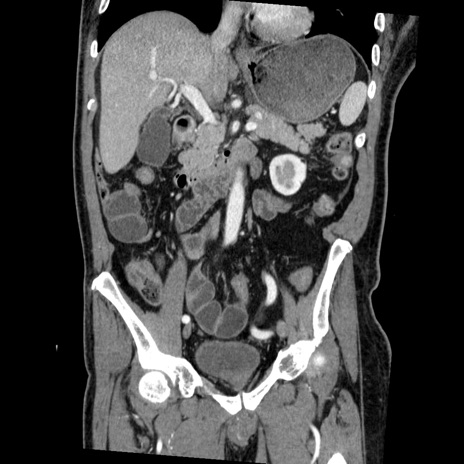

横断像

【症例】50歳代男性

【主訴】腹痛

【現病歴】AVMからの被殻出血のため回復期リハ病棟入院中。 本日午後3時頃急に下腹部痛が出現した。

【既往歴】AVM、被殻出血、虫垂炎、高血圧

【身体所見】意識晴明、左半身不全麻痺、会話の理解は良好、36.5°C、腹部:膨隆、全体に板状硬、下腹部正中に圧痛点あり、反跳痛-、筋性防御不明、右下腹部にope scar

【データ】WBC 9400、CRP 0.06